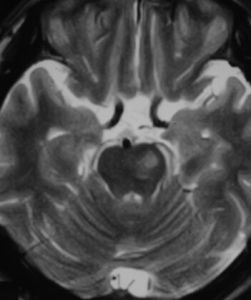

腦幹梗塞腦幹梗塞:椎基底動脈及其分支有粥樣硬化,或動脈栓塞、痙攣、炎症導致管腔狹窄、缺血而引起的循環障礙。最常見於腦橋。主要病理改變是腦軟化。多見於中老年,常常有高血壓動脈硬化或有基底動脈供血不足病史。發病較急,主要表現偏癱或四肢癱,吞咽及發音困難,高熱,意識障礙(昏迷、緘默症等)。由於受累血管不同引起不同部位的梗塞,表現各種交叉性癱瘓。腦梗塞俗稱“中風”或“腦卒中”。“中風”分為“出血性中風”和“缺血性中風”,“缺血性中風”即腦梗塞,它包括腦血栓形成、腦栓塞等,腦梗塞在所有中風中占70%至80%,近幾年來明顯增多,且向年輕化發展。有的病人僅僅27歲,但大多數為45歲以上的中老年。 腦梗塞的主要病理變化是在腦動脈硬化的基礎上,血管內形成血栓,阻塞了血流,造成腦組織的缺血、缺氧和壞死,使病人出現偏癱、失語、偏側肢體麻木、走路不穩、大小便失禁、精神錯亂、痴呆、甚至成為植物人,部分腦幹梗塞和大面積腦梗塞可致命。早期治療、早期干預可以改善病人預後,減輕和減少致殘。因為大量臨床資料表明,發病後6小時內經過有效的溶栓治療,可以使血栓溶解血管再通、使腦梗塞痊癒率達到70%至80%,個別資料報導可達近90%,不留有任何後遺症。 [治法]:益氣和血,通絡降脂,活血,化痰 [藥方]:黃芪30 丹參20 廣地龍12 川芎15 赤芍12 當歸15膽南星10 白芍12 石菖蒲15 葛根20 水蛭10 山楂18 首烏20 [化裁]:1.肝陽偏亢者,加天麻10 鉤藤12 2.血壓偏高者,加夏枯草18 石決明20 3.痰多者,加天竺黃12 4.大便乾結者,加大黃10 5.出現面癱者,加全蠍10 附子8 6.失語者,加遠志12 鬱金12 7.上肢不遂者,加桑枝15 薑黃12 8.下肢不遂者,加桑寄生15 杜仲15